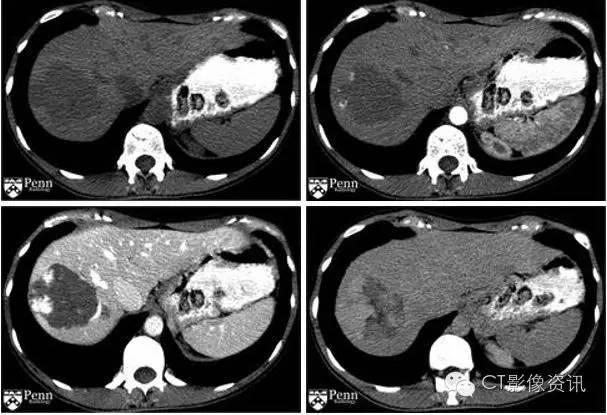

征象 CT平扫表现为右肝顶6cm低密度病灶,增强早期(动脉期)呈边缘结节状强化,并且随增强时间的延长,造影剂向中心逐渐填充。

最终诊断:海绵状血管瘤

CT征象 在平扫图像上,海绵状血管瘤表现为圆型的或者有分叶的、边界清楚的低密度病灶。 在增强图像上,海绵状血管瘤通常(在增强早期)表现为边缘的结节性或者不连续性强化,在延时期图像上呈向心性填充。 这种强化征象是由于造影剂通过多重供血血管进入病灶,并且慢慢的填充而造成的。 一些区域几乎没有强化,可能是因为存在瘢痕性或者囊液性病变。 在大于3cm的海绵状血管瘤中,病灶中心瘢痕形成是典型的表现,这可能是由肿瘤中心局部缺血或者出血造成的结果。 巨型海绵状血管瘤也可能由于局部血栓形成而表现为不均匀强化。